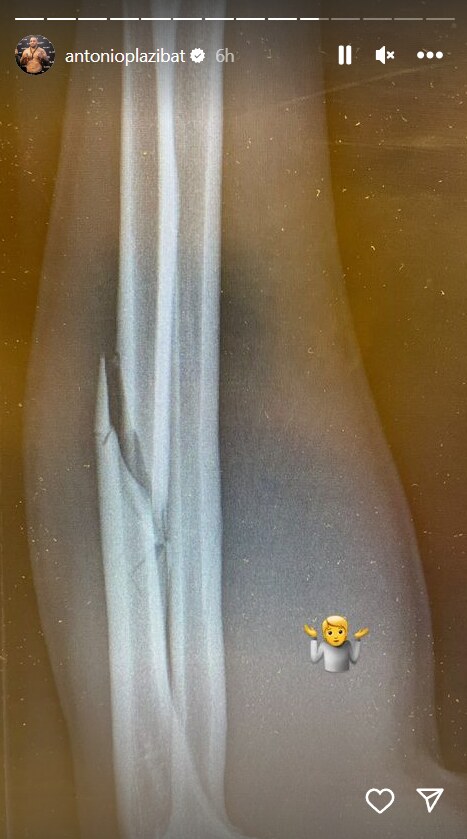

Plazibat je nakon poraza, odlaska u bolnicu i snimanja na rendgenu pokazao pratiocima na društvenim mrežama mesto na kojem mu je ruka pukla! Očigledno je nigerijski borac znao gde da napadne Antonija, pa mu je snažnim udarcima po rukom polomio taj deo tela i odmah nakon borbe ga naterao u bolnicu, a pored toga mu napravio i dodatne probleme.

Hrvatski kikbokser Antonio Plazibat polomio ruku tokom meča

Foto: Instagram/antonioplazibat/printscreen